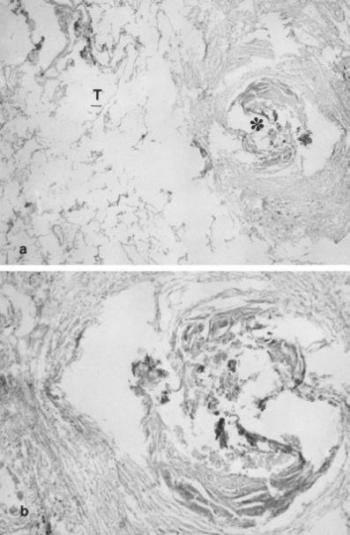

114. ábra. a) Elhegesedett, spontán gyógyult tbc-s góc (csillag), kisfokú meszesedéssel b) Az előbbi felvétel kinagyított részlete. A= 100×, B= 300× nagyítás, HE festés. 19. század, 60 éves férfi